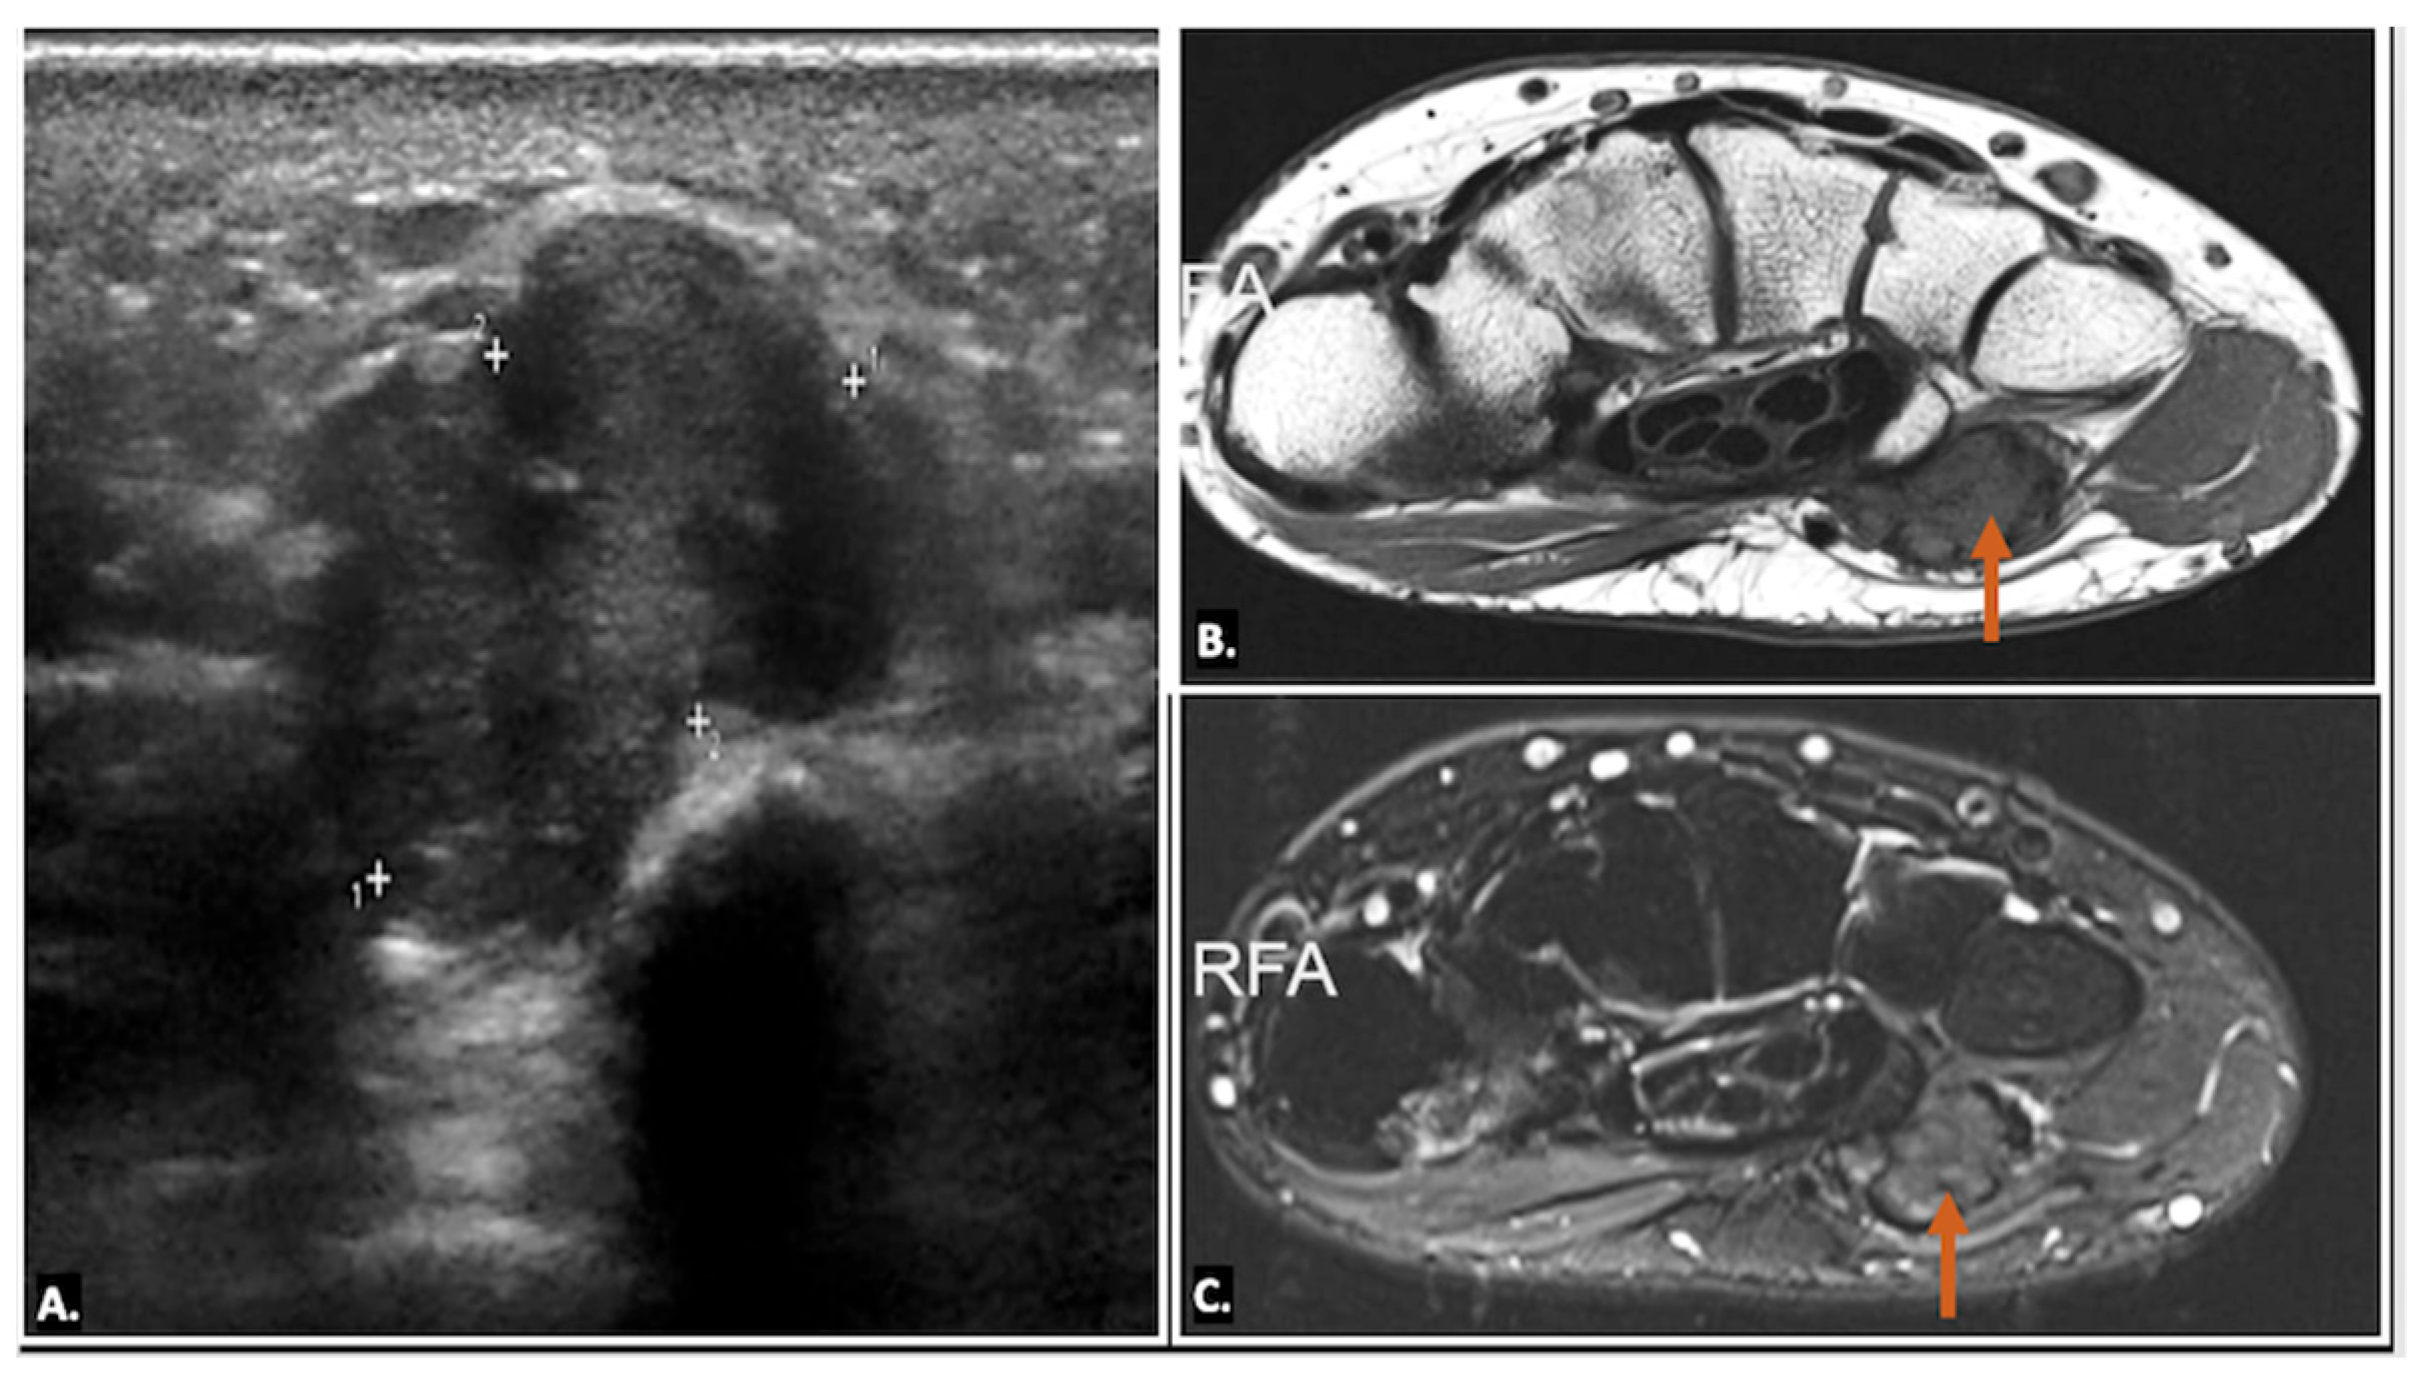

Ultrasound imaging is often the first and typically the only imaging modality required to diagnose a ganglion cyst. On ultrasound imaging, ganglion cysts appear as well-circumscribed anechoic or hypoechoic lesions with posterior acoustic enhancement. They may also show communication with nearby joints or tendon sheaths, which helps confirm their origin. Doppler ultrasound is useful to exclude the possibility of a vascular lesion, such as an aneurysm, by demonstrating an absence of blood flow within the cyst. Additionally, internal signals within the lesion on Doppler may raise suspicion for a sinister aetiology, such as a sarcoma, warranting further investigation (Figure 6) (Video S1) [13,14].

Figure 6.

(A) Axial and (B) longitudinal colour Doppler ultrasound image showing an anechoic cystic lesion within Guyon’s canal, displacing the ulnar artery—likely a simple ganglion cyst.

On MRI, ganglion cysts are well defined, hypointense on T1-weighted images, and hyperintense on T2-weighted images, reflecting their fluid content. Post-contrast images may show thin peripheral enhancement, but the cyst itself does not enhance. Unlike more complex cystic lesions, ganglion cysts usually do not contain calcific foci or haemorrhage. The cyst can cause displacement or compression of the ulnar nerve, which may show an increased signal on T2-weighted images, indicating oedema (Figure 7) [15].

Figure 7.

MRI reveals a well-defined, fluid-filled lesion within Guyon’s canal, consistent with a ganglion cyst (orange arrow), causing compression of the ulnar nerve (UN) (yellow arrow). Image (A) shows an axial view, while image (B) presents a long-axis view.

Ultrasound imaging also plays a key role in the minimally invasive treatment of ganglion cysts. For aspiration, the patient is positioned similarly to the diagnostic ultrasound scan, and the area around the expected puncture site is cleaned with an antiseptic solution. An 18-gauge needle is often required, as the cyst contents tend to be thick and gelatinous. Despite multiple attempts, the contents may not be easily aspirated in some cases, requiring the clinician to repeatedly puncture the cyst wall to facilitate resolution. Even with successful aspiration, ganglion cysts are prone to recurrence. An intralesional steroid is often administered after aspiration to reduce the risk of recurrence. This approach provides effective symptom relief while minimising the need for surgical intervention (Figure 8) [16,17].

Figure 8.

The image demonstrates ultrasound-guided aspiration of a ganglion cyst, with the needle carefully positioned within the cyst under real-time ultrasound visualisation to ensure precise targeting and safe fluid drainage (A). Graphic overlaying the ultrasound image (B).